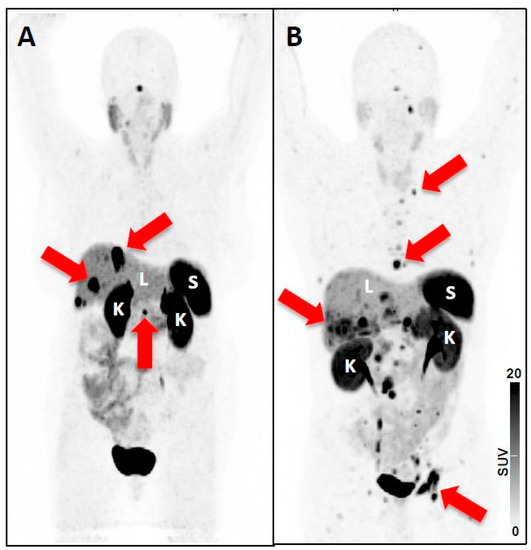

| 5 | - Intense uptake in a liver lesion with definitive findings on conventional imaging [20] | - Extensive metastatic PC with diffuse osseous metastatic disease and intense radiotracer uptake (“superscan“ on PSMA-PET/CT) [19] | |